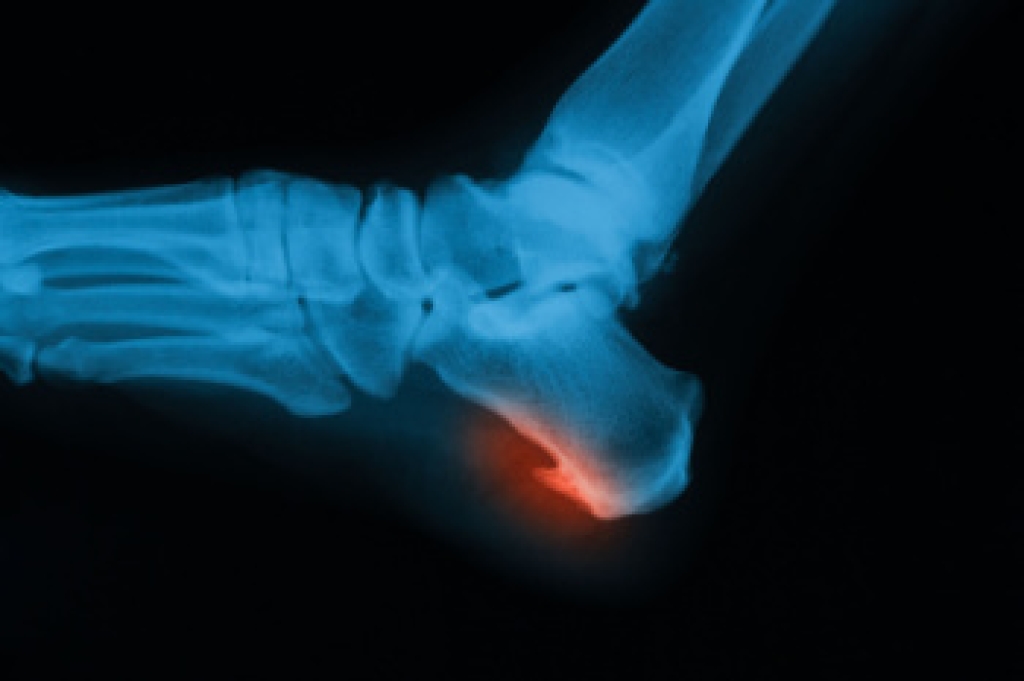

Gout is a type of arthritis caused by a buildup of uric acid crystals in the joints, often affecting the big toe, but also the foot and ankle. Symptoms include sudden, severe pain, redness, swelling, and warmth in the affected joint, making walking or standing difficult. Risk factors include a diet high in purines, obesity, genetics, alcohol consumption, and certain medical conditions. Repeated gout attacks can lead to joint damage, decreased mobility, and long-term discomfort. A podiatrist can diagnose gout, recommend lifestyle adjustments, prescribe medication, and provide care to reduce pain and prevent future attacks. Early intervention helps protect joint health and improve mobility. If you have gout symptoms in your big toe or foot, it is suggested that you promptly consult a podiatrist who can help you to manage this painful condition.

Gout is a type of arthritis caused by a buildup of uric acid in the bloodstream. It often develops in the foot, especially the big toe area, although it can manifest in other parts of the body as well. Gout can make walking and standing very painful and is especially common in diabetics and the obese.